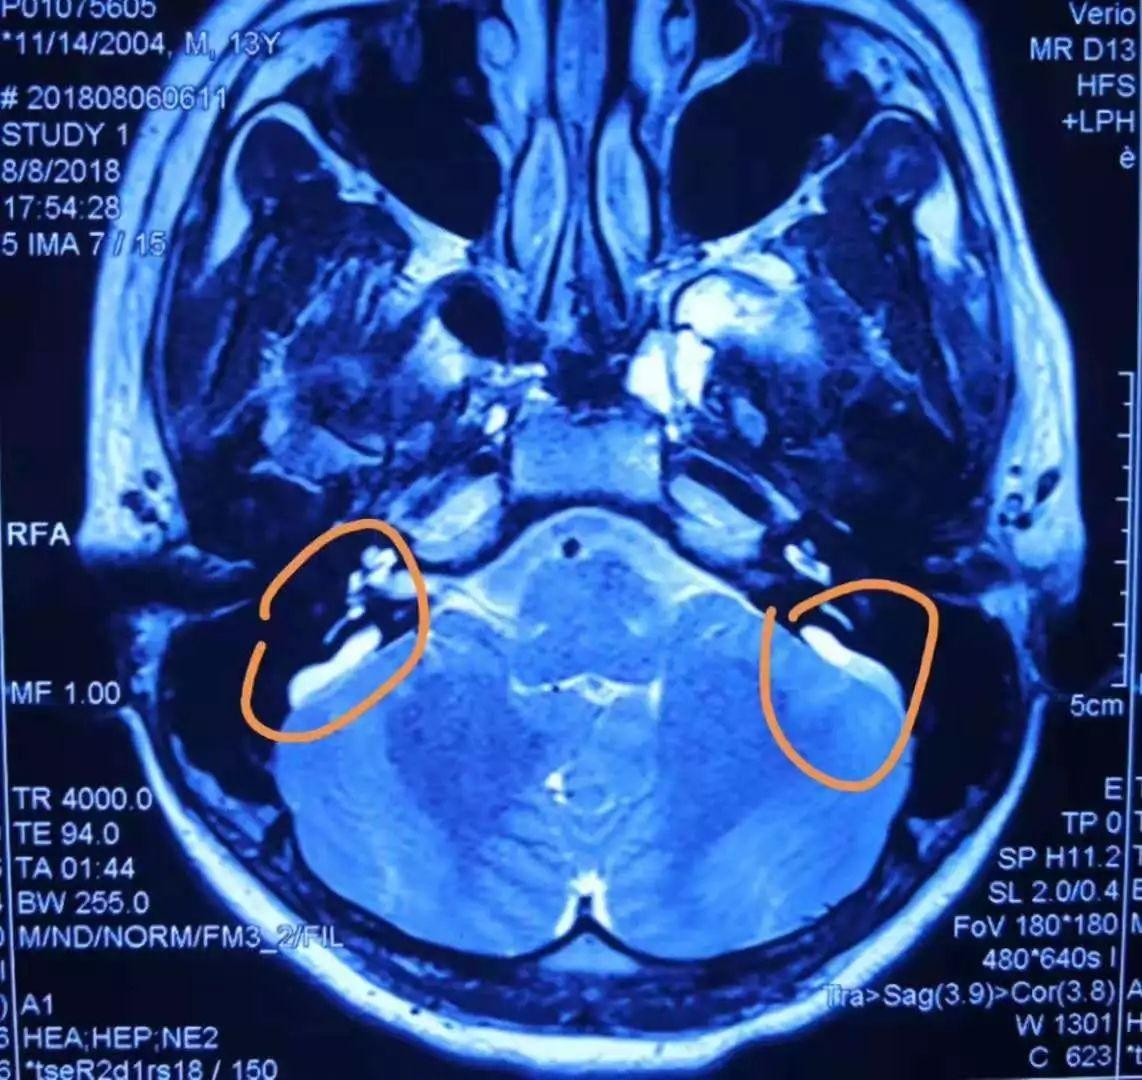

颞骨高分辨率ct示双侧前庭导水管扩大并与前庭池相通(图1a).